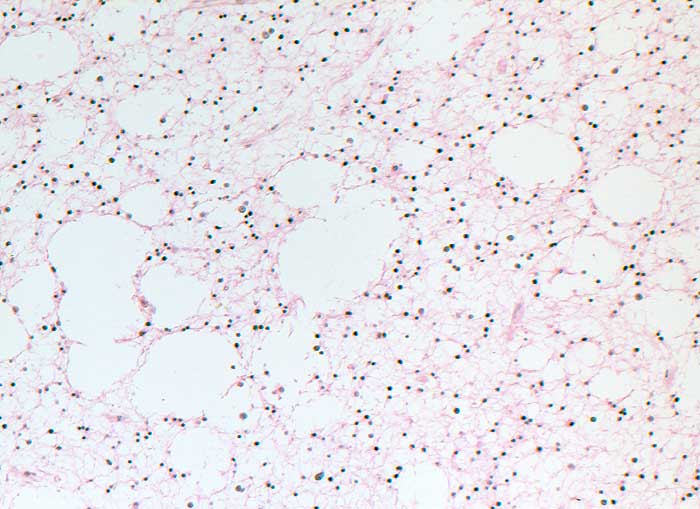

n/ Astrozytom WHO Grad II

Astrozytom WHO Grad II

Die Waschflüssigkeit ist eher zellarm. Die Ausstriche erscheinen sauber. Den Hintergrund bildet eine feinfasrige Matrix vermischt mit Nervenzellen, normalen und reaktiven Gliazellen. Die astrozytären Tumorzellen sitzen typischerweise Kapillarachsen auf. Endothelhyperplasie und Kapillarproliferate sind im Ausstrich gut zu sehen. Das Zytoplasma ist unscharf und bildet feine fasrige Fortsätze. Die Tumorzellkerne sind rund bis oval oder angedeutet spindelig, das Chromatin feingranulär. Zellgrösse, Polymorphie und Kernatypie nehmen mit abnehmender Differenzierung zu.